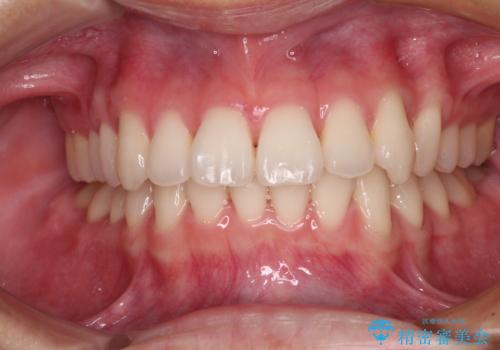

思っていたよりも早くクロスバイトは改善され、歯髄壊死に至ることなく、無事に治療を終えることができました。

- 治療期間

- 1年6ヶ月